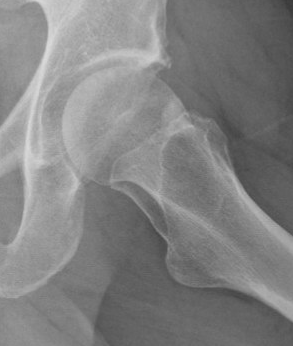

Osteopoikilosis

Rare inherited benign condition characterised by multiple bone islands

AD inheritance, high penetrance

Lesions clustered around joints

- typically arms, legs and pelvis